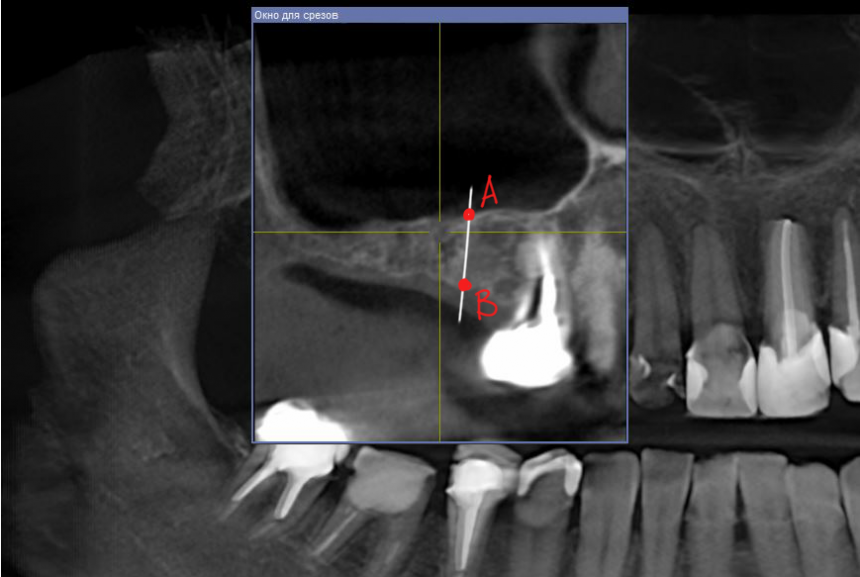

Анализ клинической ситуации

Конусно-лучевая компьютерная томография позволяет не только субъективно оценить состояние области предполагаемой операции, но и провести расчеты, необходимые для ее планирования.

Для этого производятся необходимые измерения. Основное значение имеет расстояние от нижней точки дна верхнечелюстного синуса до наиболее выступающей точки альвеолярного гребня, проведенное перпендикулярно плоскости смыкания зубов (рис 15):

Рисунок 15. Расстояние между точками А и В является основным критерием планирования операции.

Расчет производится следующим образом:

- Расстояние между точками А и В больше или равно длине импланта, который предполагается установить в данную область (10-11 мм). Синуслифтинг не требуется.

- Расстояние между точками А и В больше 3 мм. За редким исключением, этого достаточно, чтобы стабилизировать имплантат длиной 9-11 мм. Это значит, что операция синуслифтинга может проводиться одновременно с имплантацией.

- Расстояние между точками А и В менее 3 мм. Как правило, в этих условиях нет возможности качественно стабилизировать имплантат. Следовательно, операцию синуслифтинга нужно проводить отдельным этапом.